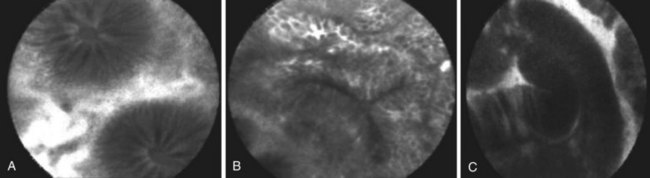

大量研究支持将基于内窥镜和探头的 CLE 系统作为在各种临床环境中进行体内组织病理学研究的新工具,包括结直肠肿瘤(图58.2)、巴雷特食管和溃疡性结肠炎。研究表明,CLE 系统可以准确区分发育不良的巴雷特食管和非发育不良的巴雷特食管在初步试点研究中,Kiesslich 和同事46根据共聚焦血管和细胞特征制定了胃粘膜、肠上皮化生和肿瘤上皮的标准。它能够预测巴雷特食管发育不良与非发育不良,敏感性为 93%,特异性为 98%。

图 58.2 A–C,正常结肠粘膜、增生性息肉和管状腺瘤的共聚焦内镜图像(基于探针的共聚焦激光内镜)。